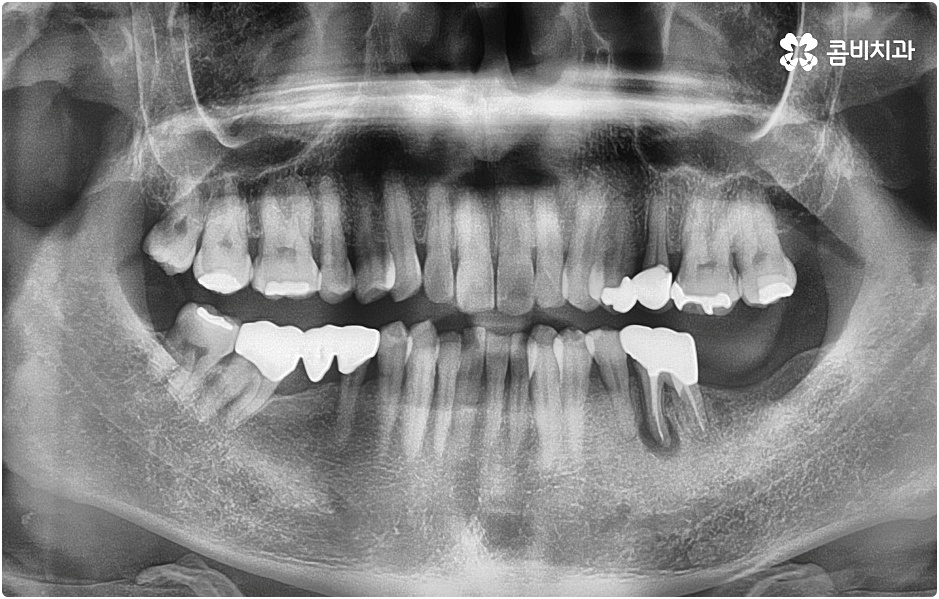

임플란트 시술을 받을 때 치아를 상실한 원인이 무엇인지, 상실하고 나서 그대로 둔 시간이 얼마나 되는지, 현재 치아나 잇몸 등 구강 내부 상황이 어떤지 등등을 먼저 꼼꼼하게 파악할 필요가 있는데요. 예를 들어 20대임플란트 를 받게 된 원인이 사고와 같은 외부 충격으로 인한 것이고 시간이 많이 흐르지 않은데다 다른 구강 질환 (충치나 치주 질환) 이 크게 문제가 되지 않는 상황이라면 젊은 나이이기 때문에 바탕이 되는 잇몸뼈 건강이 비교적 양호할 것이라고 예상할 수 있으며 이런 경우 즉시 임플란트 방식을 검토해 볼 수 있어요. 면밀한 정밀 검사 후 가능하다는 의료진의 진단이 내려진다면 당일에 인공 치근을 심고 임시 크라운까지 올려 바로 사용할 수 있는 즉시 임플란트 방식을 통해 보다 빠르고 간편하게 수복을 할 수 있습니다.

그러나 나이가 젊다고 해도 만약 치아를 상실한 원인이 심각한 구강 질환으로 인한 것이거나 치아를 잃고 나서 오랜 시간 방치를 하였거나 평상시에 당뇨 또는 고혈압 등을 앓고 있었다면 환자분의 잇몸뼈 건강이 양호하지 않을 수 있으며 그런 경우에는 즉시 임플란트 시술을 받을 수 없고 먼저 뼈이식 과정을 통해서 잇몸뼈를 보충해 준 다음 20대임플란트 식립을 진행하는 것이 정확도와 지속성을 높여주는 방법이라고 할 수 있어요.

그러나 언급했던 것처럼 잇몸뼈 상태에 대해서 먼저 체크해 봐야 하기 때문에 누구나 받을 수 있는 치료 과정은 아니라는 점을 분명히 알아두실 필요가 있습니다. 이렇게 잇몸뼈를 보충해야 하는 상황 뿐 아니라 충치 또는 치주 질환을 먼저 깨끗하게 치료해야 하는 상황, 상악동까지의 거리가 너무 짧아서 거상술을 통해 혹시 모를 천공과 염증을 방지해야 하는 상황 등 여러 가지 선치료가 필요한 케이스들이 있을 수 있기 때문에 먼저 환자분들의 상황을 자세하게 파악하기 위해서 꼼꼼한 검진을 해 볼 필요가 있으므로 3D CT 등 정밀 검진 장비 보유 여부가 필수적이라고 말씀드린 거예요.

그러나 치아가 빠진 후부터 잇몸뼈는 수축을 하기 시작하기 때문에 오랜 기간 그대로 방치를 하게 되면 잇몸이 내려앉아 주변 치아가 쓰러지고 치열이 흩뜨러지며 악관절까지 좋지 않은 영향을 받게 되는 등 구강 내부적으로 문제가 더 커질 수 있으며, 치아가 크게 부러진 뒤 치근이 일부 남아 있는 상황이라고 하더라도 기능을 전혀 하지 못하여 주변 치아와 잇몸에 지속적인 부담을 주고 있거나 해당 부위를 통해 감염이 일어날 가능성이 높다면 이를 발치하고 빠르게 기능적 심미적 대체를 해 줄 필요가 있으니 될 수 있는대로 바로 치과로 내원하셔서 검진부터 꼼꼼하게 받아보시고 그에 적합한 치료를 받으시길 권유드리고 있어요.